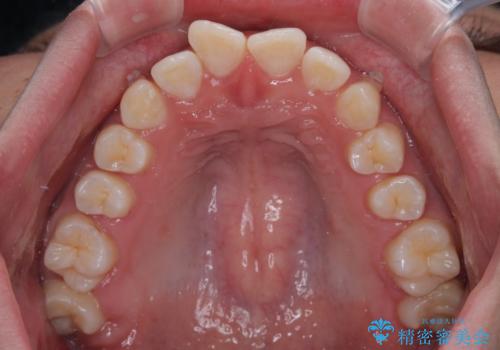

- ディープバイトと上顎前歯の突出、奥歯の咬み合わせを気にして来院された患者様です。

上顎歯列は全体的に前方位にあり、それが原因で深い咬み合わせとなり、突き上げにより上顎前歯が前方に飛び出している状態でした。

また、左右ともに上顎最後臼歯が頬側に転位している鋏状咬合となっていました。

インビザラインによる矯正治療をご希望でしたが、上顎歯列の前方位と鋏状咬合を確実に改善することを目的として、補助装置を併用することとしました。

補助装置を併用せずに治療を終える可能性はありましたが、確実に結果を得るために補助装置を活用しました。

イメージしたとおりの仕上がりとなりました。